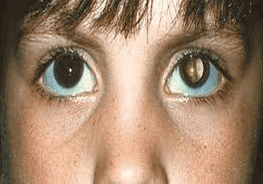

- Early morning vomiting or persistent headache, changes in eye, abnormal gait